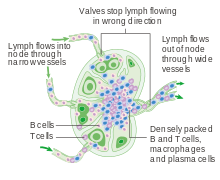

Diagram of a lymph node, showing the flow of lymph through the lymph sinuses. | |

A lymph node is an oval- or kidney-shaped organ of the lymphatic system, present widely throughout the body including the armpit and stomach and linked by lymphatic vessels. Lymph nodes are major sites of B, T, and other immune cells. Lymph nodes are important for the proper functioning of the immune system, acting as filters for foreign particles and cancer cells. Lymph nodes do not deal with toxicity, which is primarily dealt with by the liver and kidneys.

Lymph nodes are kidney or oval shaped and range in size from a few millimeters to about 1–2 cm long.[4] Each lymph node is surrounded by a fibrous capsule, and inside the lymph node the fibrous capsule extends to form trabeculae. The substance of the lymph node is divided into the outer cortex and the inner medulla. The cortex is continuous around the medulla except at the hilum, where the medulla comes in direct contact with the hilum.[4]

Thin reticular fibers and elastin form a supporting meshwork called a reticular network inside the node. White blood cells (leukocytes), the most prominent ones being lymphocytes, are tightly packed in the follicles (B cells) and the cortex (T cells). Elsewhere in the node, there are only occasional leucocytes. As part of the reticular network there are follicular dendritic cells in the B cell follicle and fibroblastic reticular cells in the T cell cortex. The reticular network not only provides the structural support, but also the surface for adhesion of the dendritic cells, macrophages and lymphocytes. It allows exchange of material with blood through the high endothelial venules and provides the growth and regulatory factors necessary for activation and maturation of immune cells.[5]

Lymph enters the convex side of the lymph node through multiple afferent lymphatic vessels, to flow through the sinuses. A lymph sinus which includes the subcapsular sinus, is a channel within the node, lined by endothelial cells along with fibroblastic reticular cells and this allows for the smooth flow of lymph through them.The endothelium of the subcapsular sinus is continuous with that of the afferent lymph vessel and is also with that of the similar sinuses flanking the trabeculae and within the cortex. All of these sinuses drain the filtered lymphatic fluid into the medullary sinuses, from where the lymph flows into the efferent lymph vessels to exit the node at the hilum on the concave side.[4] These vessels are smaller and don't allow the passage of the macrophages so that they remain contained to function within the lymph node. In the course of the lymph, lymphocytes may be activated as part of the adaptive immune response.

The cortex of the lymph node is the peripheral portion underneath the capsule and the subcapsular sinus.[6] The subcapsular sinus drains to trabecular sinuses, and then the lymph flows into the medullary sinuses.

The outer cortex consists mainly of the B cells arranged as follicles, which may develop a germinal center when challenged with an antigen, and the deeper cortex mainly consisting of the T cells. There is a zone known as the subcortical zone where T-cells (or cells that are mainly red) mainly interact with dendritic cells, and where the reticular network is dense. The predominant site within the lymph nodes which contain T cells & accessory cells is also known as paracortex (reticular network).[7]

The medulla contains large blood vessels, sinuses and medullary cords that contain antibody-secreting plasma cells.

The medullary cords are cords of lymphatic tissue, and include plasma cells, macrophages, and B cells. The medullary sinuses (or sinusoids) are vessel-like spaces separating the medullary cords. Lymph flows into the medullary sinuses from cortical sinuses, and into efferent lymphatic vessels. Medullary sinuses contain histiocytes (immobile macrophages) and reticular cells.

Lymph circulates to the lymph node via afferent lymphatic vessels and drains into the node just beneath the capsule in a space called the subcapsular sinus. The subcapsular sinus drains into trabecular sinuses and finally into medullary sinuses. The sinus space is criss-crossed by the pseudopods of macrophages, which act to trap foreign particles and filter the lymph. The medullary sinuses converge at the hilum and lymph then leaves the lymph node via the efferent lymphatic vessel towards either a more central lymph node or ultimately for drainage into a central venous subclavian blood vessel.